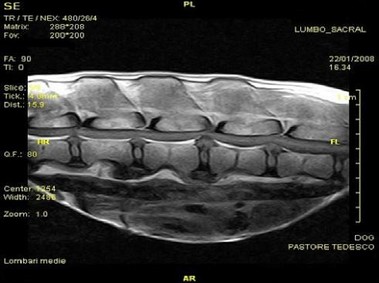

В настоящее время МРТ является наиболее предпочтительным методом визуализации любых мягких тканей, особенно для визуализации травм и патологий центральной нервной системы и суставов. Особенности Vet-MR позволяют использовать данный метод визуализации также в сфере ветеринарии.

Vet-MR специально разработана для визуализации небольших животных и является результатом внимания к деталям при разработке магнита, катушки и электронных компонентов, обеспечивая высокое качество экономически эффективной и простой в использовании МРТ в сфере ветеринарии.